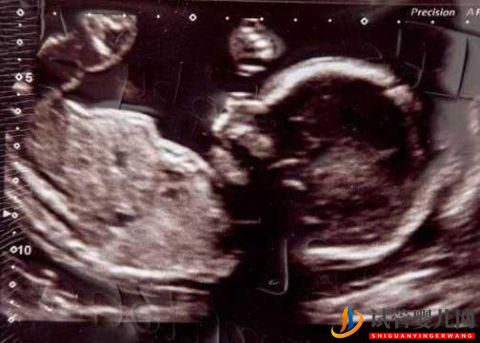

夫婦拒絕NHS(英國國家醫(yī)療服務(wù)體系)試管受精治療,反而去借£10,000(約合9萬元)的現(xiàn)金貸。但現(xiàn)在必須償還£24,000(約合22萬元)的現(xiàn)金。現(xiàn)年已經(jīng)48歲的孕媽Carolyn,花了23年努力懷孕。下個月她終于要迎來自己的第一個寶寶。她和34歲的丈夫Michal表示,對這筆現(xiàn)金貸巨額貸款毫不后悔。

借了利率高達(dá)49.9%的現(xiàn)金貸,未來五年他們倆必須償還£23,715的現(xiàn)金。作為NHS的管理者的Carolyn,找到了現(xiàn)金貸公司Amigo,給她資助了六輪試管受精費用。令她高興的是,她懷孕了并將于下個月生下一個名叫Kayleigh的女兒。“我一點也不后悔。如果不是貸款,我現(xiàn)在都不會懷孕”